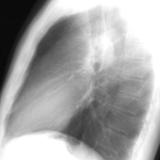

ASD 1 Lat

Date: 03/17/2004

Views: 2492